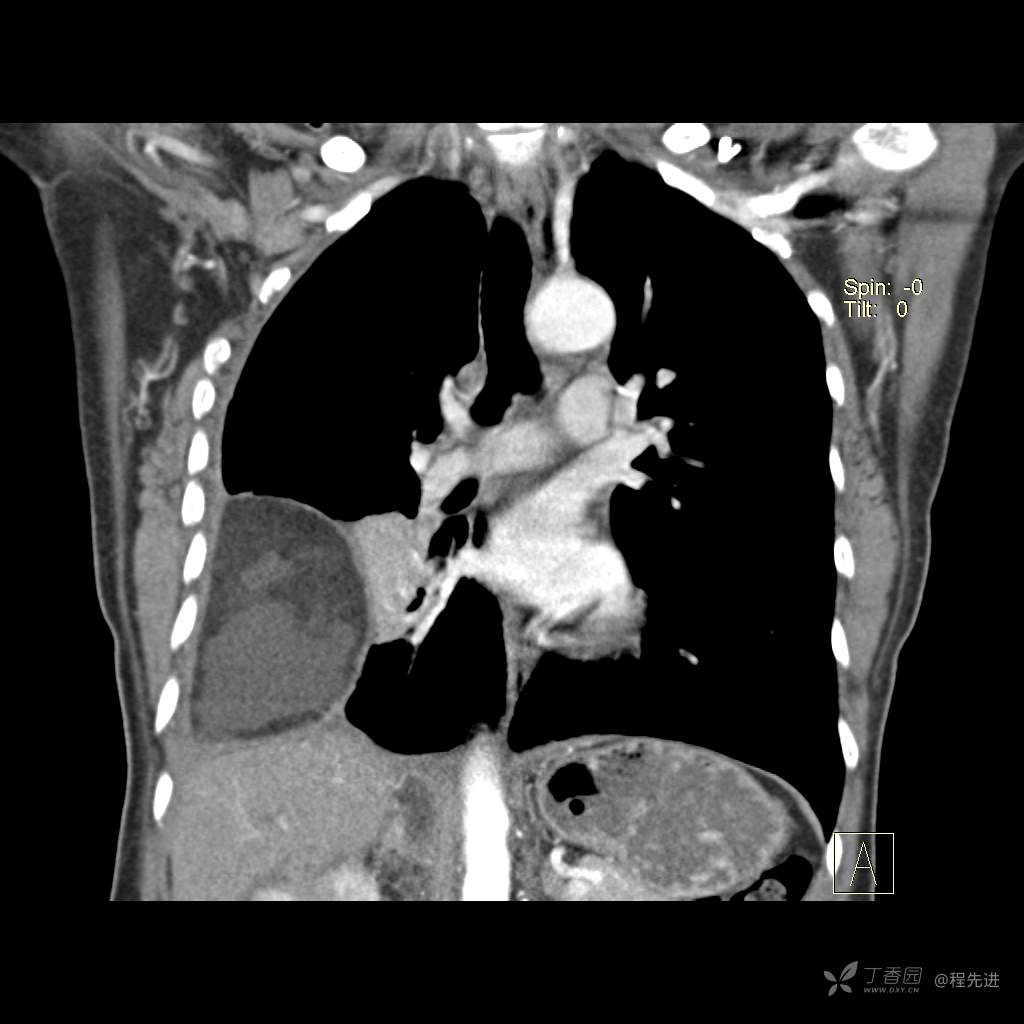

患者性别:女

患者年龄:51岁

简要病史:胸闷半年

肺淋巴管肌瘤病 (7)

乳糜胸 (8)